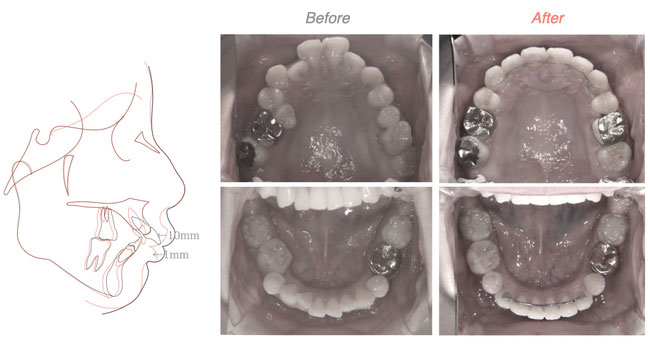

根の治療で治らない歯がある方や、抜歯してブリッジ、入れ歯と言われた方で不要な親知らずがある方にとっていい治療法となるかもしれません。ご参照ください。

かぶせものの精度は的確か、歯石の取り残しはないか、根の中はどうなっているのか、すべて口の中を見ただけでは分かりません。患者さんには分からない箇所であるからこそ、そこにこだわった歯科医院でありたいと思います。自分の行った治療の経過を追うこと以外にいい歯科医になる方法はないと信じております。お口の中の写真を撮ってもらったことはありますか?治療の必要性を、予後を説明されたことはあるでしょうか?当院では記録を大事にし治療の経過を追いかけてより良い医療を提供しようと考えております。